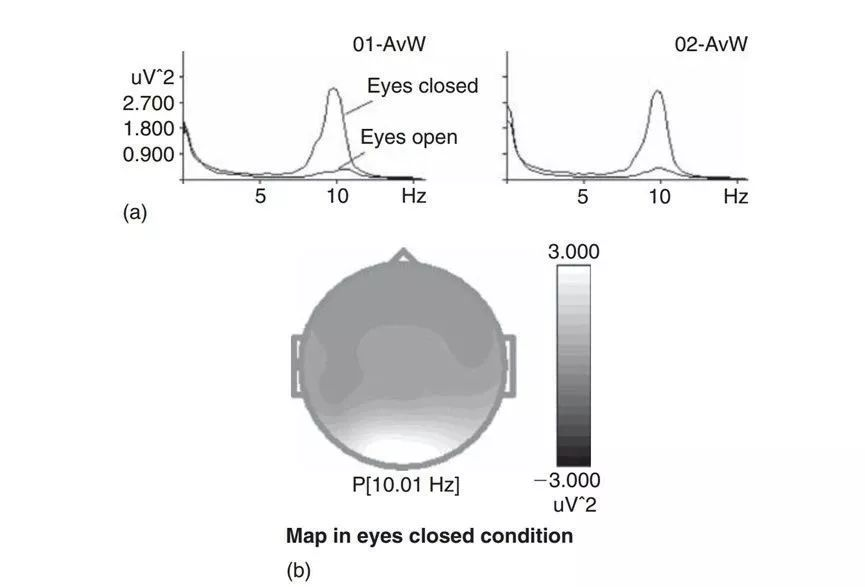

如图2所示,被试在睁眼状态下可以在O1和O2脑区观察到显著的alpha节律;被试O1和O2电极的alpha节律一般是同步化的,但是对于某些健康被试来说,O1和O2的alpha节律可能是相互独立的。此外,当被试闭眼清醒状态时,枕叶alpha节律会大幅度增强,如图3所示。

图3